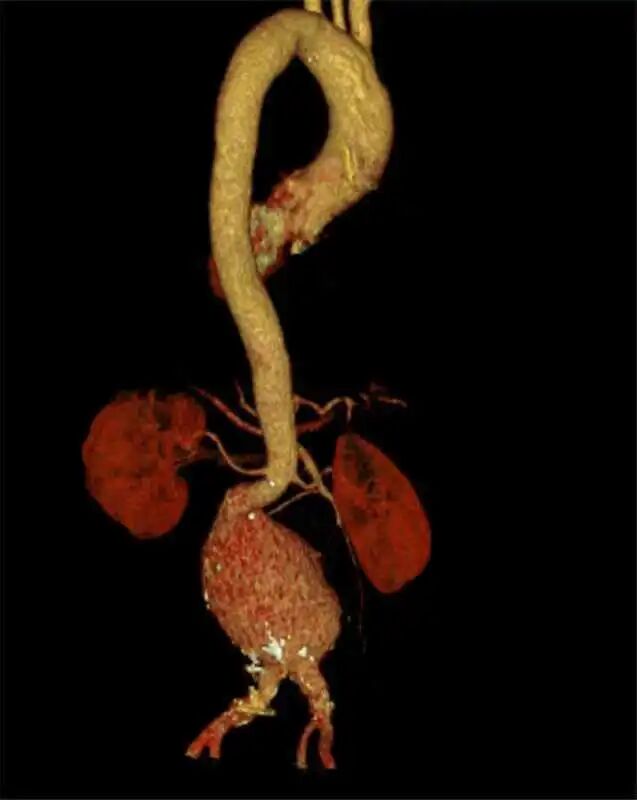

检查结果证实了孔主任的判断:李嗲腹主动脉中下段有一个直径达10cm的巨大动脉瘤伴壁间血肿,超过正常血管直径的3-4倍。

术前影像